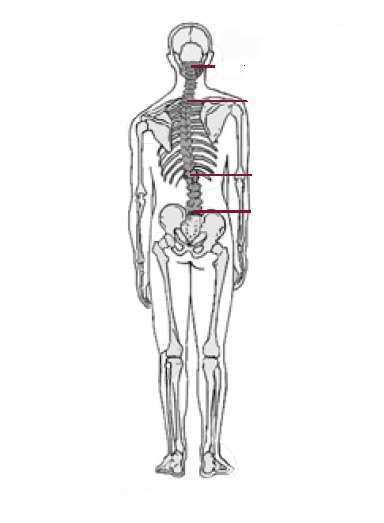

우리 몸은 척추가 틀어지면 보상을 하게 되는데 짧아진 다리길이 차이로 인해 한번만 보상이 일어났다면 같은 쪽 어깨가 낮아 보이겠지만 흔히 보상은 2회이상 일어나므로 반대쪽 어깨가 낮아 보이는 경우도 매우 많습니다.

체형을 평가 하는 데는 두 가지 사진이 필요하다 ; 측면과 전후면-- 전후면 자세에서 척추를 보면 측면과 측면의 균형을 보게 된다. 측면에서는 척추의 만곡을 볼 수 있다.

여러가지 체형변화가 일어나지만 거의 대부분 공통적으로 거북목 현상이 일어납니다. 거북목이란 몸통에 비해 목이 앞으로 빠져 나오는 현상을 말하는데 위의 그림에서 중심중력선이 귀를 지나가야 하지만 비정상적인 체형시에는 중심중력선이 귀를 통과하지 못함을 볼 수 있습니다.

체형은 전체적 관점에서 봐야 합니다. 빙산의 일각을 놓고 저거 삐져 나와서 잘못되었으니 저거 잘라 놓고 보자는 식은 안 된다는 것입니다. 일자목과 거북목의 치료는 결국 골반과 허리부터 치료해야 합니다. 그리고 전체적인 좌우, 전후의 중심중력선이 일치되는 방향으로 치료해야 합니다.